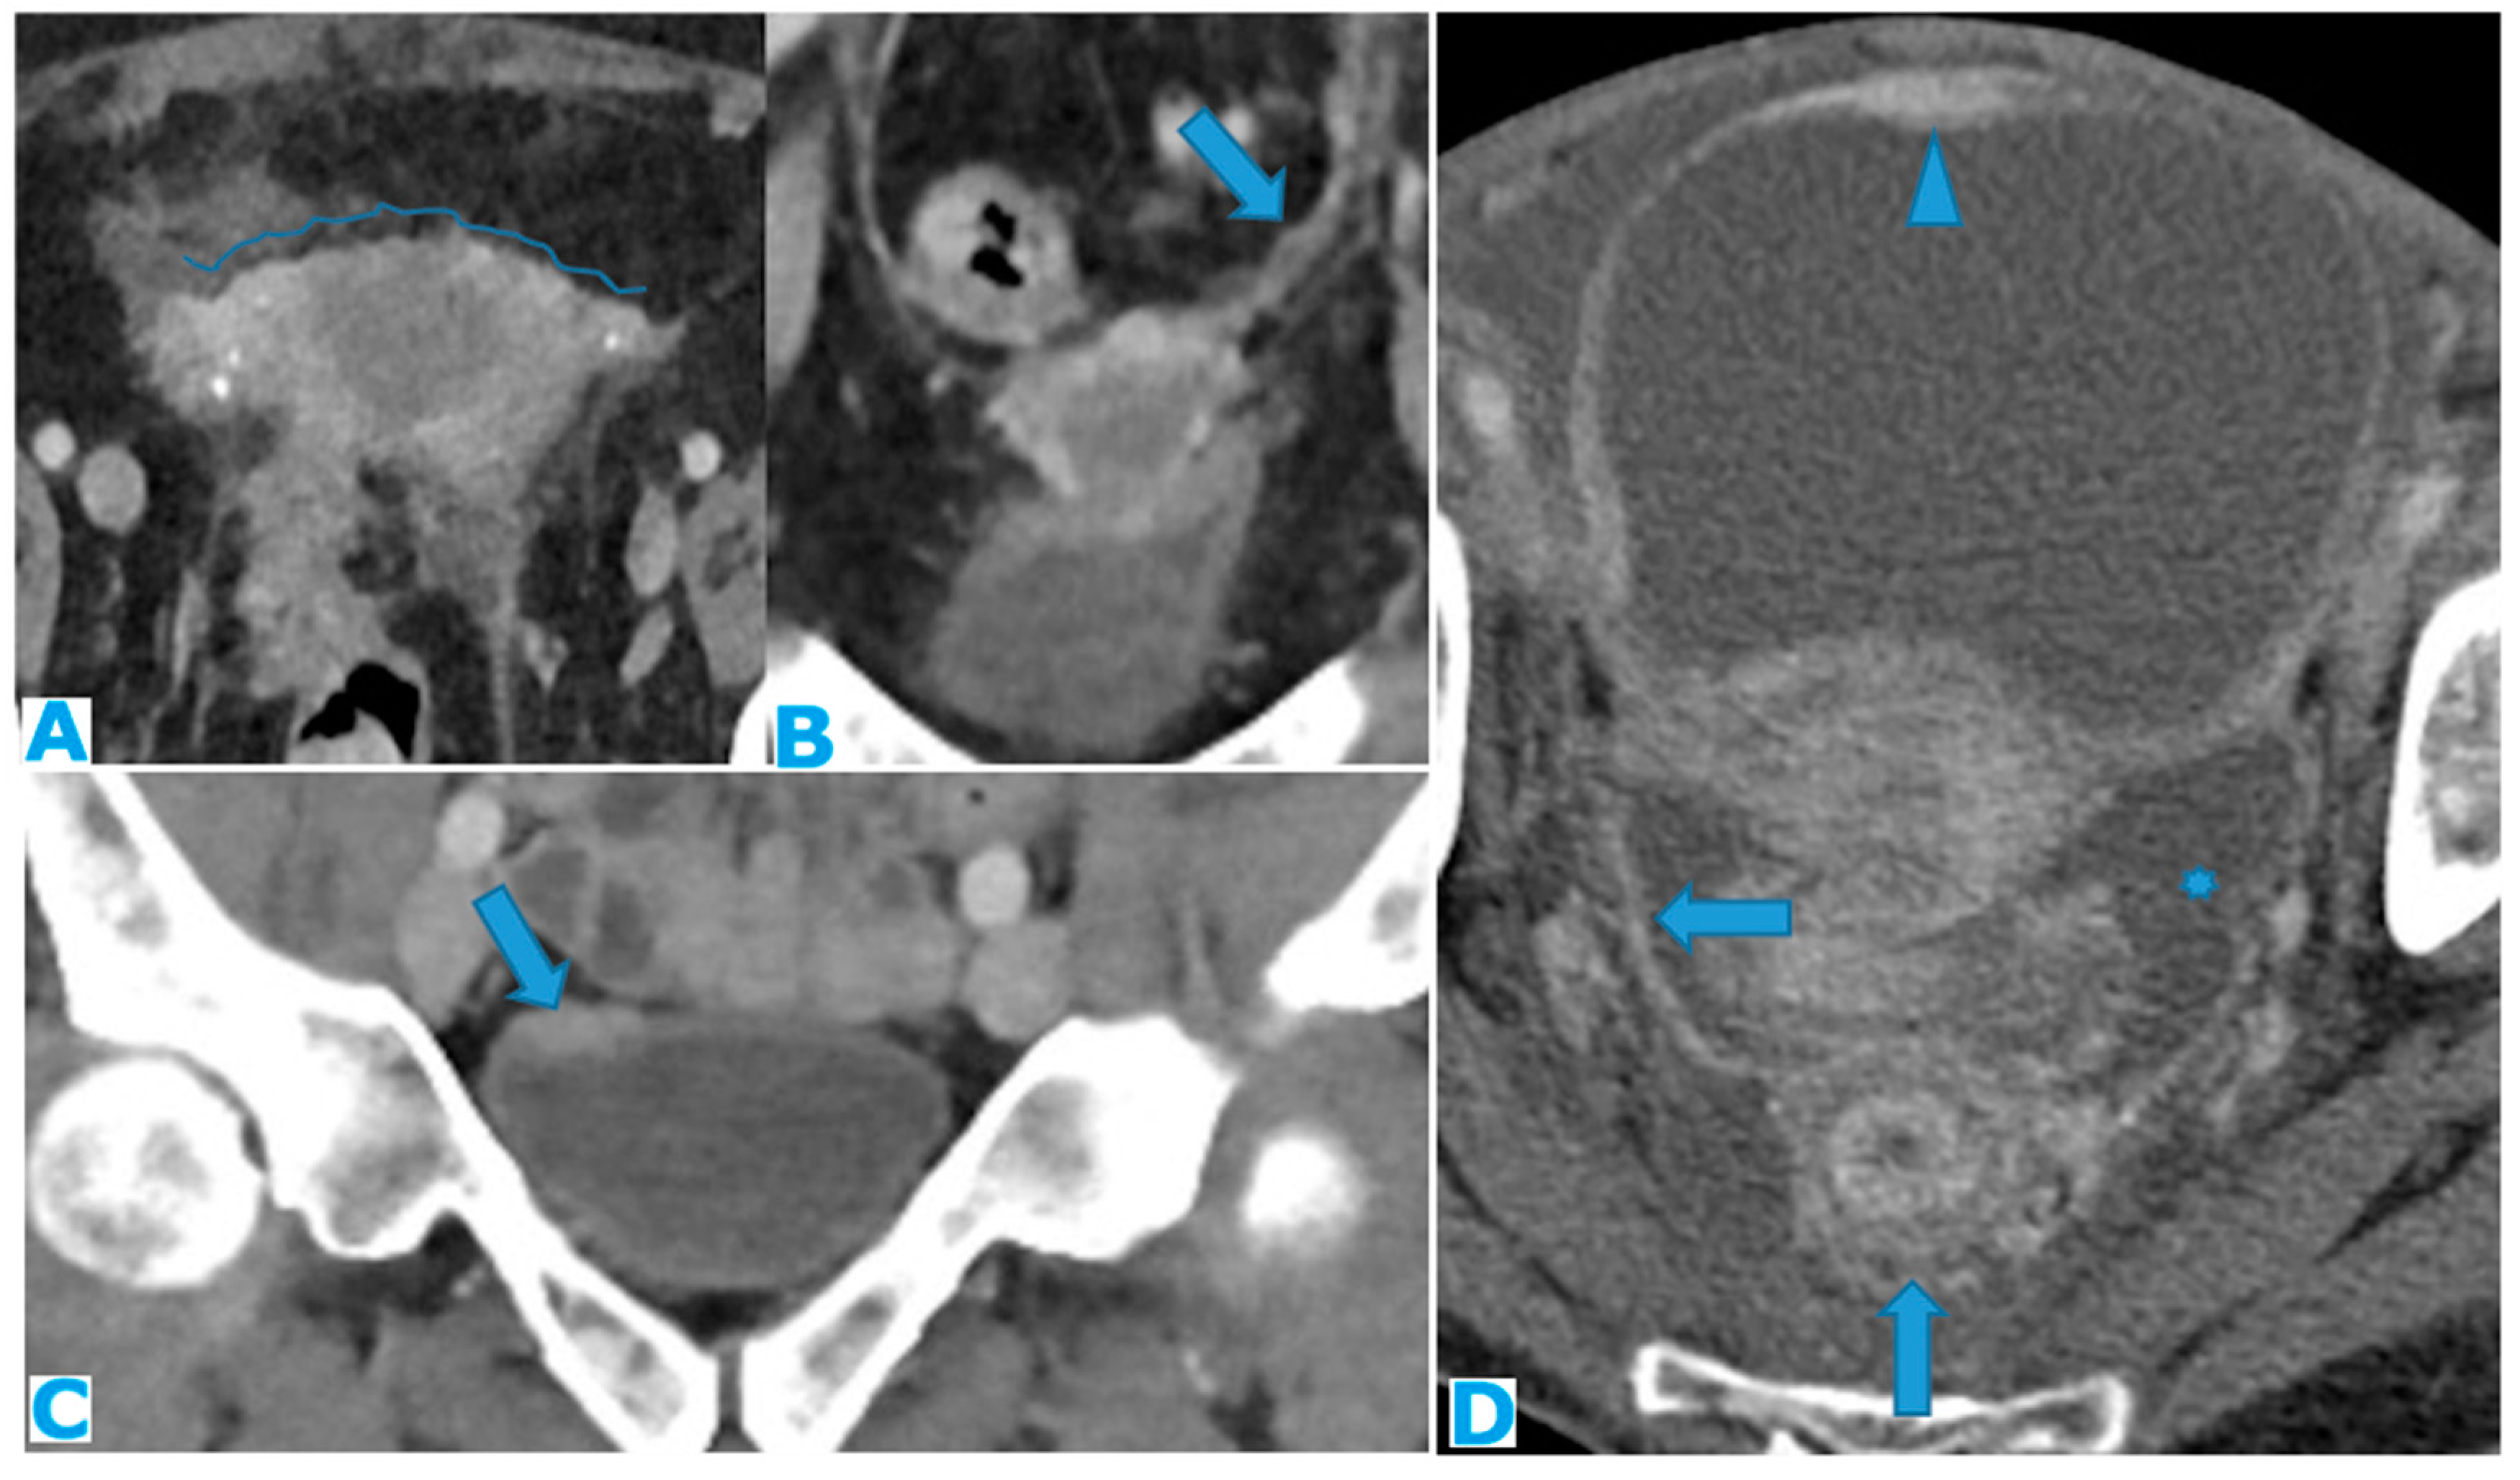

Figure 26.

Axial CE-CT (A). PC from stomach adenocarcinoma: Stellate mesentery. Axial CE portal phase FST1WI (B). PC from lobular breast adenocarcinoma: Stellate mesentery, notice the perivascular distribution. Axial CE-CT (C), axial T2WI (D). PC from stomach adenocarcinoma: Isolated perivascular deposit within the mesentery, as a soft tissue mass surrounding a branch of the SMV.